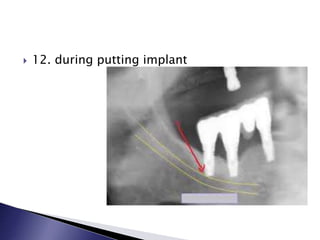

 12. during putting implant

 12. duringputting implant